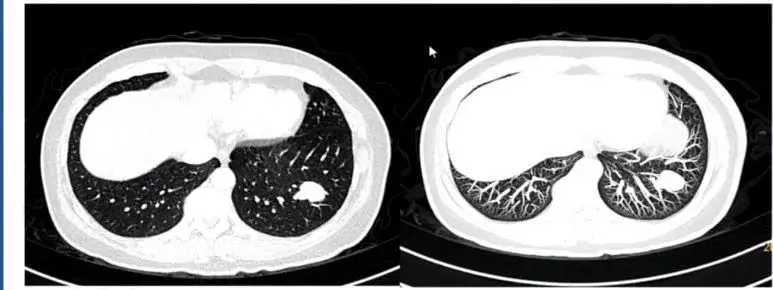

9. 球形肺不张

大量胸腔积液吸收后易出现出现球形肺不张。肺内结节有实性密度增高表现,并带有“尾巴”。

1599963495357_fc3e0b43j00qgk3gi000yd200lq008og00g2006e.jpg

图12 球形肺不张